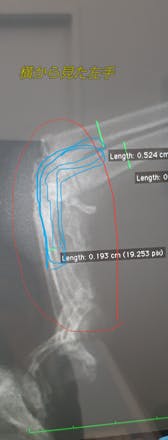

水色で囲ってところを杖のようにしっかりつけるようにプレートで固定する手術です。

この手術をしないと、無理に着いているところから骨が露出してしまい、壊死や感染症が起こり、断脚しなければならなくなるようです。